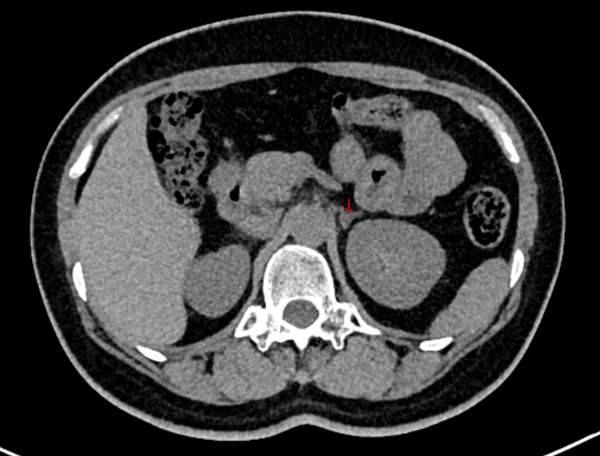

但是真凶藏在哪里?CT结果出来了,左侧肾上腺体部增粗,超过同侧膈脚厚度,增强扫描其内可见5.1x6.5mm弱强化区,边缘尚示清晰。右侧肾上腺形态规则,内外侧肢体内未见异常密度影。真凶就在左侧肾上腺。故而我们完美收官,该患者诊断原发性醛固酮增多症——醛固酮瘤 继发性高血压。我们建议患者手术治疗。